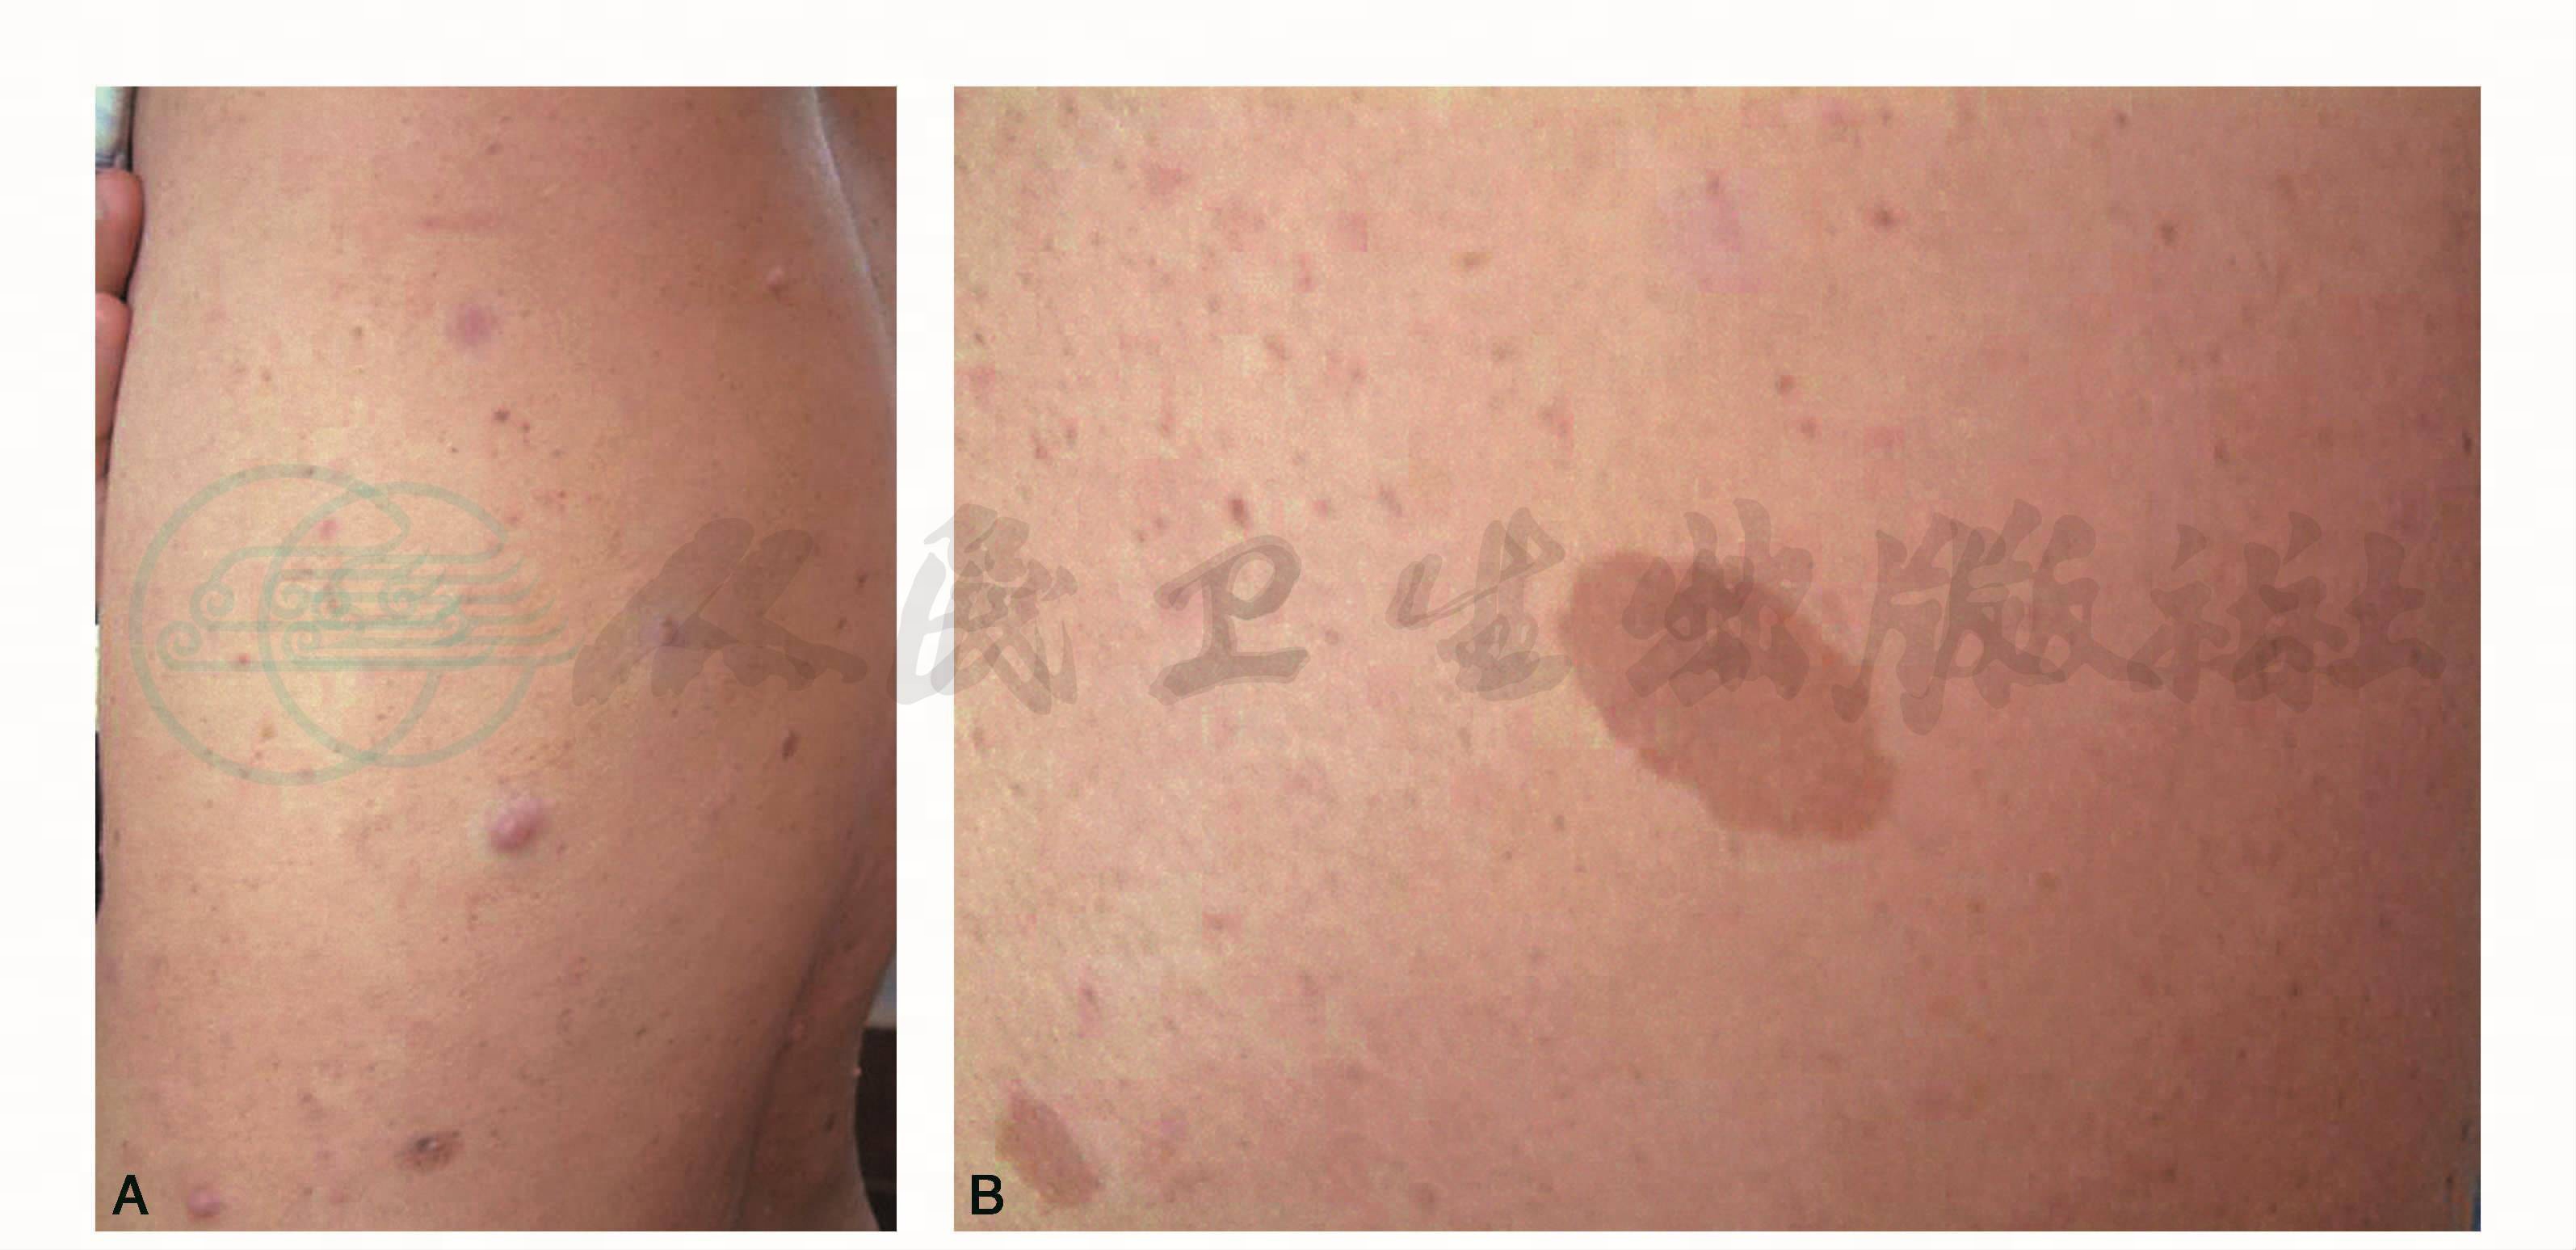

皮肤多发棕色色素斑(图1A、B);T2WI(图1C、D)见双侧胸锁乳突肌深面多发结节、肿物,信号增高,欠均匀,边缘清楚;T1WI为等信号(图1E);增强后结节、肿物强化明显(图1F~I);其中双侧听神经、右侧海绵窦旁可见结节状强化。

图1 颈部多发神经纤维瘤病

A~B.多发棕色色素斑;C~D. T2WI横断位;E. T1WI横断位;F~G. T1WI增强横断位;H、I. T1WI增强冠状位;J. HE×200